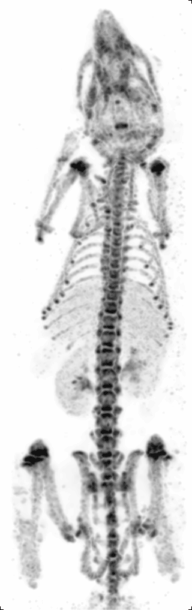

Principle: Similar to PET, Single Photon Emission Computed Tomography (SPECT) also images living systems through γ-rays emitted from within the subject. Unlike PET, the radioisotopes used in SPECT (such as technetium-99m) emit γ-rays directly,[10] instead of from annihilation events of a positron and electron. These rays are then captured by a γ-camera rotated around the subject and subsequently rendered into images.

Strengths: The benefit of this approach is that the nuclearisotopes are much more readily available, cheaper, and have longer half-lives as compared to micro-PET isotopes. Like micro-PET, micro-SPECT also has very good sensitivity and only nanograms of molecular probes are needed.[15] Furthermore, by using different energy radioisotopes conjugated to different molecular targets, micro-SPECT has the advantage over micro-PET in being able to image several molecular events simultaneously. At the same time, unlike micro-PET, micro-SPECT can reach very high spatial resolution by exploring pinhole collimation principle (Beekman et al.) [16] In this approach, by placing the object (e.g. rodent) close to the aperture of the pinhole, one can reach high magnification of its projection on detector surface and effectively compensate for intrinsic resolution of the crystal.